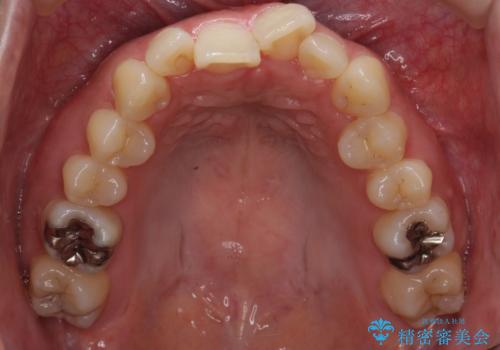

右上の奥歯を後ろに送り、前歯が出っ歯にならないように並べました。

また、右下の奥歯に一部目立たないように部分的なワイヤー矯正を行い、右下の奥歯が反対咬合になっていたのもしっかり中に入れて治療しています。

奥歯の反対咬合を治すのはインビザラインではかなり難しいのですが、しっかり治療できました。